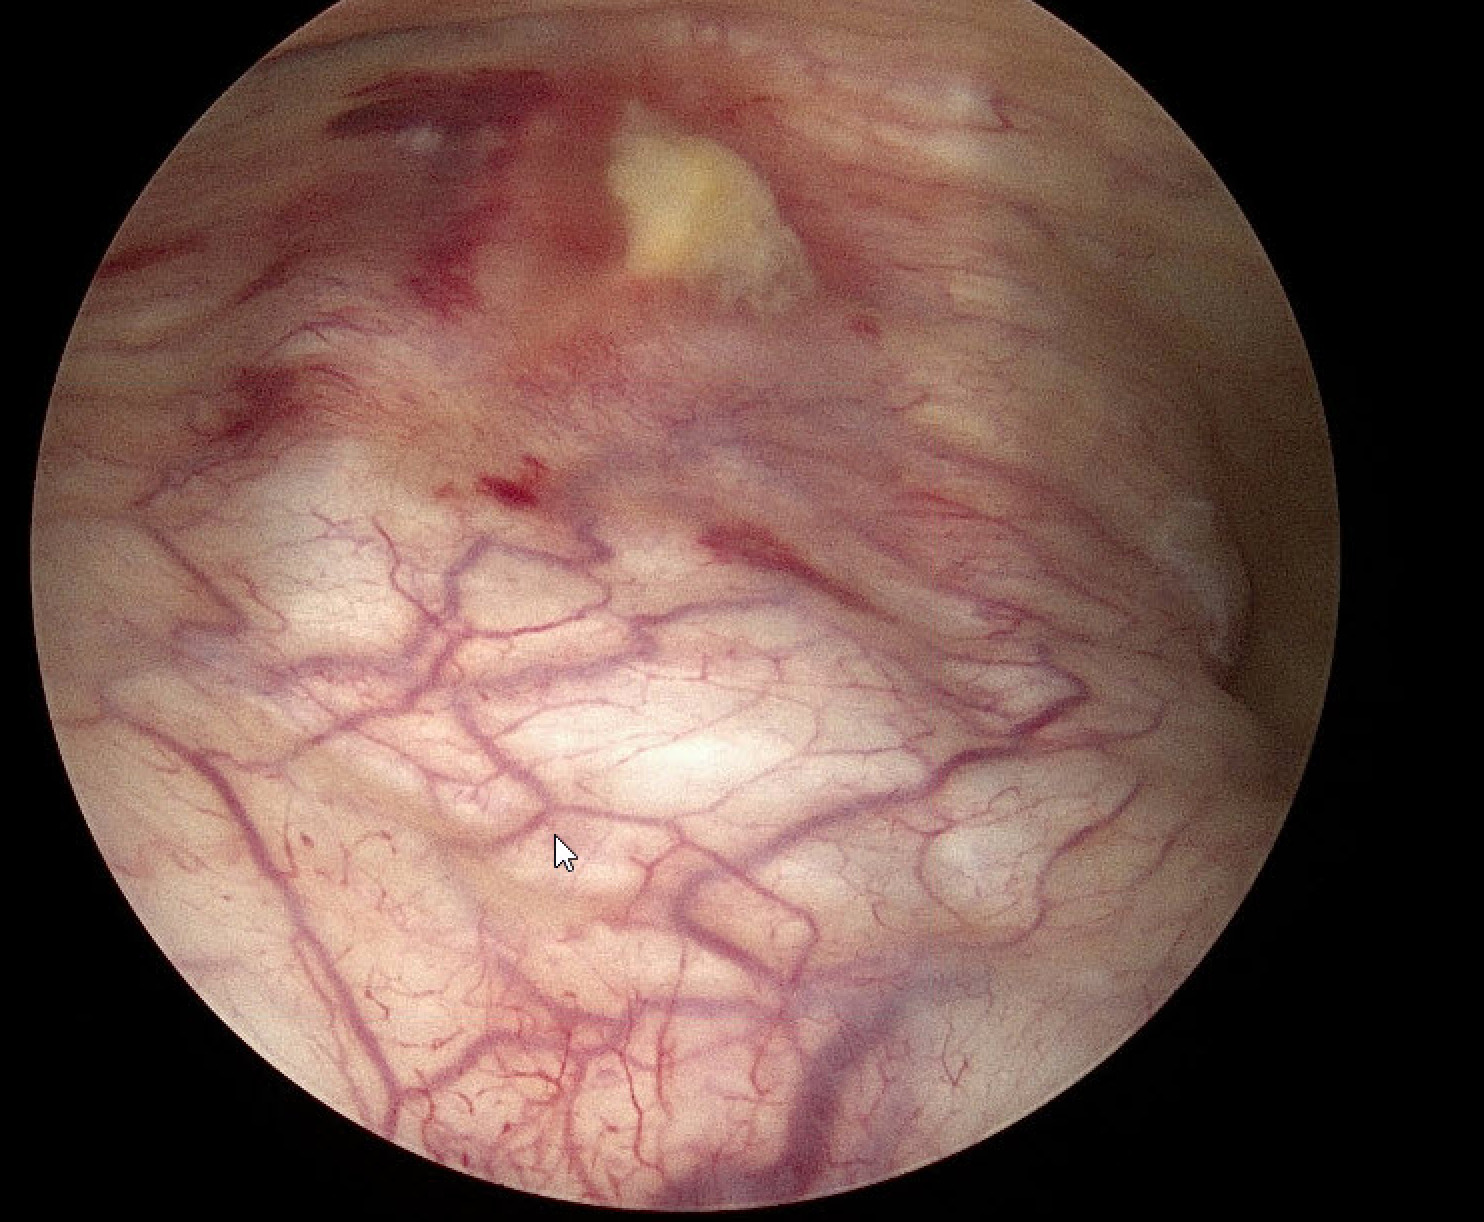

Approximately two weeks after the operation she presented at the emergency department with bladder pain of varying intensity over a period of 3 days. After ruling out urinary tract infection, and because of the severity of the symptoms a cystoscopy was performed to rule out bladder injury. Cystoscopy revealed a 1 cm thermal injury to the posterior bladder wall. This was considered consistent with cervicovesical dissection (Figure 1).

Figure 1. Thermal bladder injury sustained during cystoscopy on the 17th day postoperative.